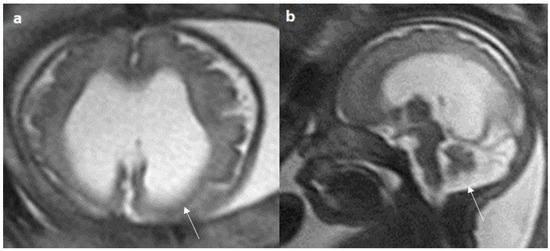

Figure 8.

Fetal MRI images of a 34 gestational weeks aged fetus, with complete agenesis of the corpus callosum and gray matter heterotopia. (a) A T2-weighted sequence image in mid sagittal plane showing complete absence of the corpus callosum with secondary changes in ventriculomegaly. (b) A T2-weighted axial sequence image showing associated subependymal heterotopia (white arrow) along the occipital horns of the bilateral lateral ventricles with moderate dilatation of lateral and third ventricles.